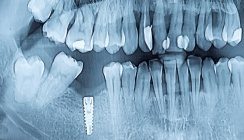

Nach einer Implantation stellt eine Infektion das größte Risiko für eine gelungene Osseointegration dar. Um diesem vorzubeugen, haben Wissenschaftler jetzt ein Implantat entwickelt, dass durch einen eingebauten Speicher kontinuierlich ein Medikament abgibt, welches das Infektionsrisiko eindämmen soll.

Um die Osseointegration eines Zahnersatzes zu erleichtern, werden in letzter Zeit verstärkt Implantate mit einer rauen Oberfläche verwendet. Allerdings haben einige Studien bereits belegt, dass sich an diesen Oberflächen auch einfacher Bakterien anlagern können. Um dieses Problem zu lösen, haben Forscher der Katholieke Universiteit Leuven in Belgien jetzt ein neuartiges Implantat entwickelt, dass einen eingebauten Speicher unterhalb der Zahnkrone besitzt. In diesen Hohlraum lässt sich ein antimikrobieller Wirkstoff füllen, der kontinuierlich nach außen strömt. Ein Drehverschluss ermöglicht die einfache Wiederbefüllung des Speichers. Der Wirkstoff verhindert die Anlagerung von Bakterien an das Implantat und so mögliche Infektionen. Erste Labortests mit dem Antiseptikum Chlorhexidin konnten bereits positive Ergebnisse erzielen. So wurde festgestellt, dass sich das Bakterium Streptococcus mutans nicht am Implantat anlagert, wenn dieses mit der Lösung befüllt ist. Auch ein vorher angelegter Biofilm am Zahnersatz konnte sich durch die Verwendung des Antiseptikums zurückbilden. Das Chlorhexidin strömte über einen Zeitraum von zehn Tagen kontinuierlich nach außen. Selbst nach 40 Tagen konnte noch eine Wirkung auf die Bakterien festgestellt werden. Ob und wann das Implantat im menschlichen Gebiss getestet wird, ist noch nicht abzusehen.